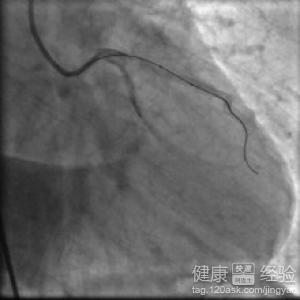

冠狀動脈粥樣硬化性心髒病吃什麼藥

概 述 冠狀動脈粥樣硬化性心髒病一般來說已經常被叫做冠心病。目前來說在我們國家發生過的動脈粥樣硬化